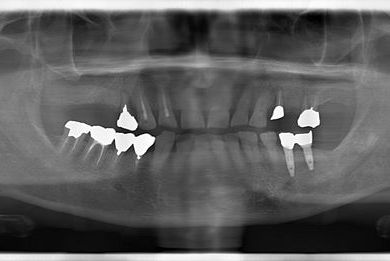

抜歯即日スピードインプラント治療+歯周外科治療

| 性別/年齢 | 男性 / 62歳 | ||||||||||||||||||||||||||||||||

| 主訴 | 左下の奥歯のブリッジがゆれて、痛みがある。 | ||||||||||||||||||||||||||||||||

| 治療方針 | 抜歯と同時にインプラント埋入を行い、治療期間を短縮する。 | ||||||||||||||||||||||||||||||||

| 治療内容 | インプラント2本(抜歯即日スピードインプラント)、ハイブリッドセラミッククラウン2本、歯周外科治療 | ||||||||||||||||||||||||||||||||

| 総治療費 | 771,960円 | ||||||||||||||||||||||||||||||||

| 治療期間 | 6ヶ月 |